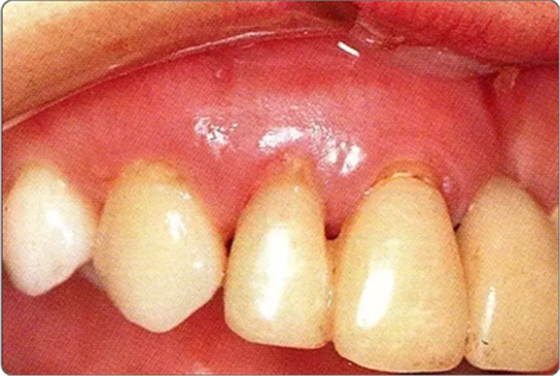

圖10-8 上頜腭側(cè)處縫合的狀態(tài)。為獲得一次性創(chuàng)傷治愈進(jìn)行了緊密縫合

圖10-9 術(shù)后2周的狀態(tài)。牙齦乳頭獲得保存。較之使用GTR膜,自體骨移植更不容易引起牙齦乳頭的壞死。